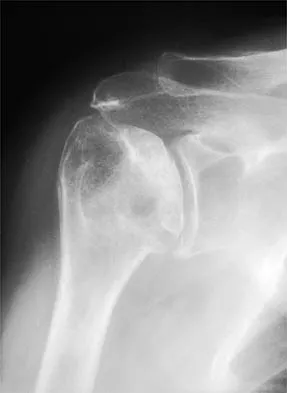

A 20-year-old patient has foot pain. A radiograph and T1-weighted MRI scan are shown in Figures 8a and 8b. A biopsy specimen is shown in Figure 8c. Treatment should consist of

Explanation

Giant cell tumors occur near articular surfaces in young adults. The histology shows abundant giant cells with nuclei resembling the surrounding cells. Although the MRI scan shows soft-tissue involvement, curettage is still the preferred treatment. Chemotherapy is not necessary for benign lesions, and amputation is too aggressive. Cementation, phenol, and cryosurgery (liquid nitrogen) are all acceptable local adjuvants to curettage. Packing the cavity with bone graft rather than cement is also acceptable. Dahlin DC, Unni KK: Bone Tumors: General Aspects and Data on 8,542 Cases. Springfield, IL, Charles C. Thomas, 1986.